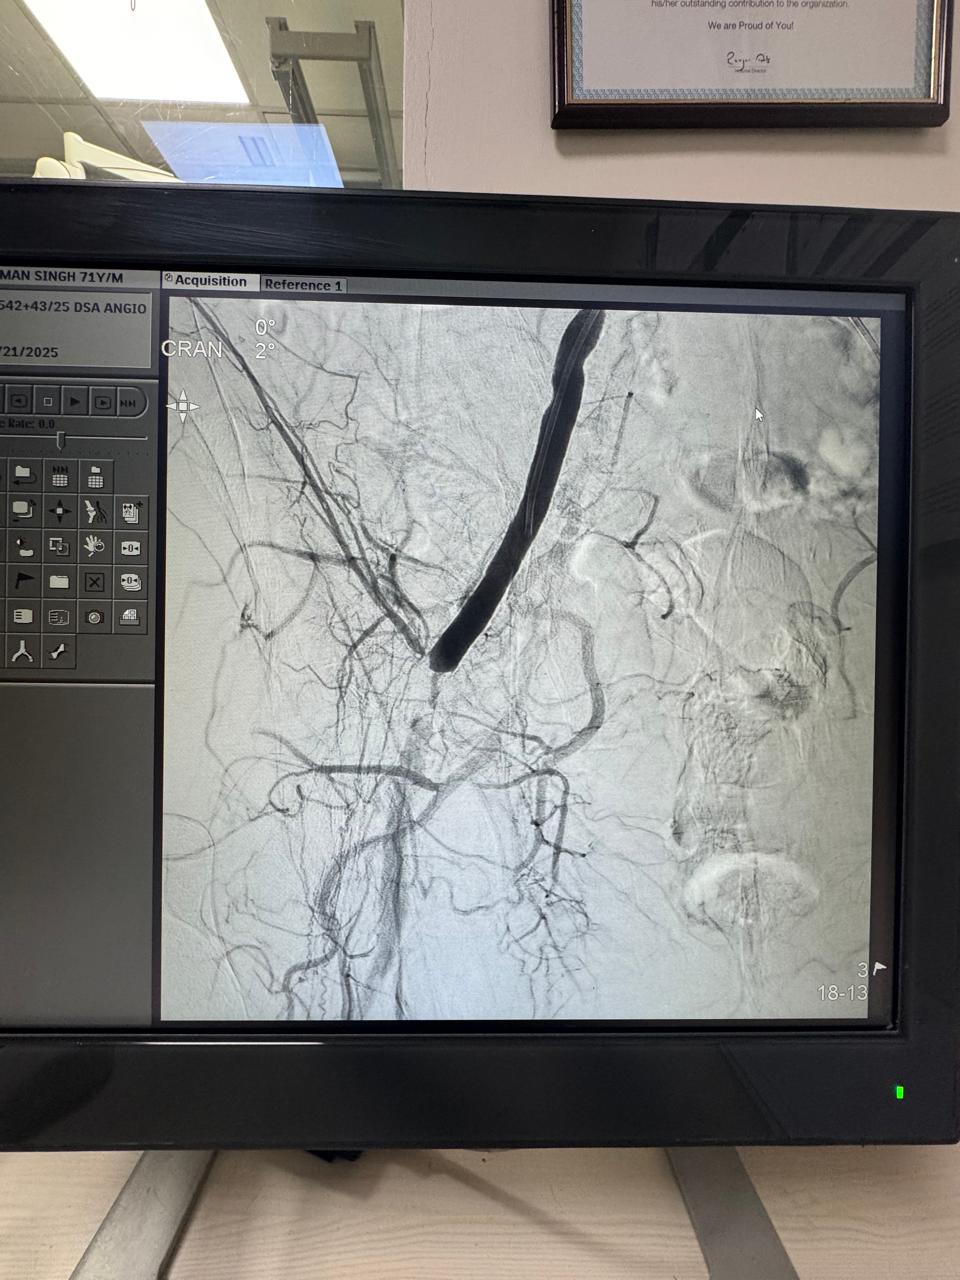

Angioembolization of traumatic right internal iliac artery ( posterior branch)injuries